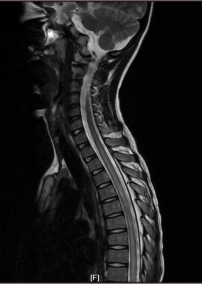

碩碩起病急、進展迅速,若不及時治療很可能發(fā)展為重癥并危及到生命。入院后醫(yī)生馬上展開救治。進行詳細查體和追問病史,及時完善抽血化驗、腰椎穿刺、頭顱+全脊髓核磁共振等系列檢查,最終,迷霧散去、真相浮出水面——碩碩患的就是急性播散性腦脊髓炎。

核磁共振影像